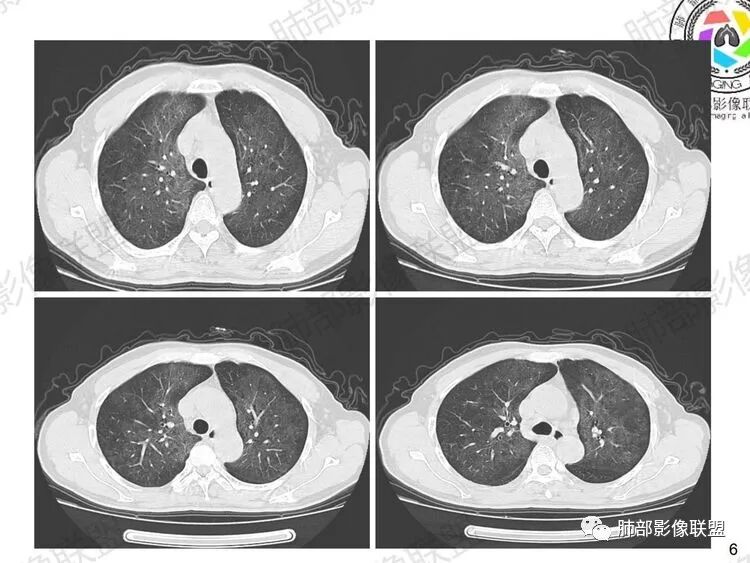

晚期:修复最终导致间质纤维化改变,双肺小叶间隔明显增厚,肺叶呈纤维状、条索状、网格状改变,支气管牵拉性扩张和蜂窝肺,HRCT病灶显示为碎石路征样改变,是本病的特征表现之一,该征象出现表示肺泡、肺间质同时受累,是病变进展的重要表现。肺气囊是肺孢子菌肺炎较常见的影像学特征,多见于晚期,多分布于肺上叶或肺周边, 也可发展到整个肺实质,其形成是由于肺实质的破坏。肺气肿可破裂引发自发性肺气胸、纵隔及皮下气肿。

PAP 典型的碎石路

④过敏性肺炎,病史上常有过敏原吸入史,影像上急性或亚急性期表现为弥漫磨玻璃影(早期肺泡炎)、小叶中心结节及空气潴留(肉芽肿炎及气道不畅),如果出现纤维化及蜂窝,则提示进入慢性期。

HP弥漫分布的小叶中心结节及空气潴留(图片来自吴婧老师)